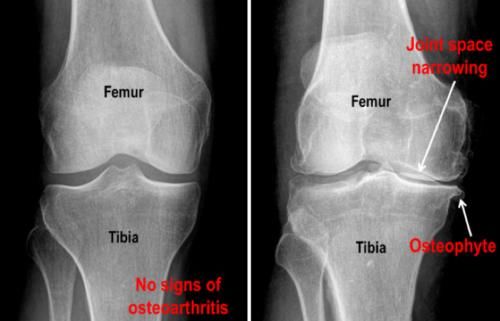

骨关节炎导致老人下肢无力也很常见!

另外一个导致老年人出现下肢无力的常见原因就是骨关节炎了,这个疾病随着年龄的增长发病率会明显的增加。这个疾病主要累及的是关节内的软骨,关节内的软骨会发生皲裂,严重的甚至会发生脱落,而关节软骨对于保护关节的光滑、对于缓冲压力有非常重要的作用,一旦发生损伤以后,慢慢的我们的身体就会用骨质增生、骨赘来替代软骨的功能,形成的骨赘比较多了,就会影响关节的功能了,也就是说好心办了坏事。

文章插图

而这些增生的骨头有可能会刺激到患者周边的肌肉、筋膜和神经,导致疼痛,疼痛会导致人们减少活动肌肉会面临萎缩,下肢无力自然就出现了。

骨关节炎患者早期会表现为膝关节的疼痛,有的患者表现为膝关节前方的疼痛,有的患者会表现为膝关节后方的紧张感,在上、下楼梯或者是蹲起的时候,会感觉关节有响声,并不一定会伴有疼痛,但如果伴有疼痛的话,说明关节软骨磨损的比较严重。

进行膝关节X线或者是核磁检查,可以帮助老年人明确是否存在骨关节炎。如果症状相对来讲比较轻,可以口服氨糖,关节内注射玻璃酸钠或者是富血小板血浆因子,以及适当的中药治疗,物理治疗等帮助老年人控制症状。而且建议老年人要适当的活动、控制体重,维持关节周边肌肉的力量,而且可以避免肌肉萎缩的形成,那人关节的力量自然也就会被控制住,而不会慢慢的变得无力。